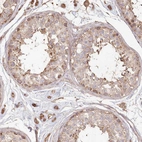

Immunohistochemical staining of human cerebral cortex, liver, skin and testis using Anti-HAL antibody HPA038547 (A) shows similar protein distribution across tissues to independent antibody HPA038548 (B).